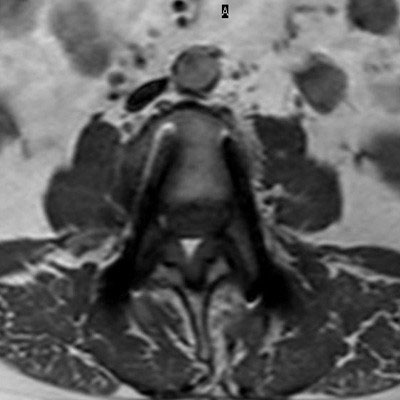

Lumbar Spine with metal implant, routine and fast

Utrecht Medical Center, The Netherlands

**Only for use with MR Safe or MR Conditional Implants by strictly following the Instructions for Use.